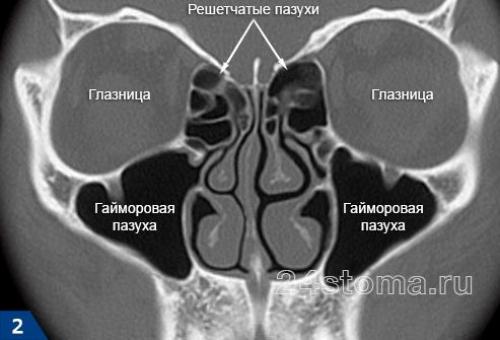

Этмоидит – это воспаление решетчатой пазухи (решетчатого синуса). Часто воспаление решетчатой пазухи называют обобщенным термином «синусит», под которым следует понимать воспаление любой из четырех пар придаточных пазух носа.

К придаточным пазухам носа (помимо решетчатой) также относят –

- гайморовые пазухи – их воспаление называется термином «гайморит» ,

- лобные пазухи – их воспаление называется «фронтит» ,

- клиновидные пазухи – их воспаление называется «сфеноидит» .

Решетчатый синус является парным (рис.1). Каждый решетчатый синус состоит из множества мелких полостей в кости (микропазух), заполненных воздухом и выстланных изнутри слизистой оболочкой. Синус имеет продолговатую форму и вытянут в передне-заднем направлении.

Важная анатомическая особенность решетчатого синуса –

микропазухи передней части синуса (расположенных ближе к поверхности лица) имеют сообщение при помощи небольшого отверстия со средним носовым ходом; микропазухи задней части синуса, расположенные ближе к основанию черепа и клиновидной пазухе, имеют сообщение с верхним носовым ходом.